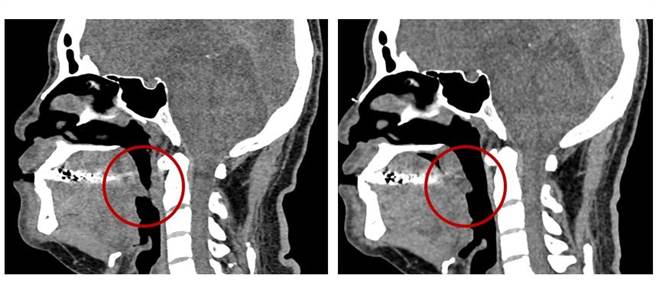

台中医院睡眠中心医师钟威升表示,睡眠呼吸中止症是容易被轻忽的疾病。人在睡眠时,上呼吸道(包括鼻咽、口咽及喉部)反覆性塌陷堵住呼吸道,使人体呼吸变浅且费力,会出现明显的打鼾声,若症状严重,会造成呼吸道完全堵塞而造成窒息。

钟威升表示,睡眠呼吸中止症治疗可多管齐下,减重能使症状得到改善,患者未能减重前可配戴「连续型正阳压呼吸器」为主,让患者在睡眠时不缺氧,也可以透过佩戴矫正器改善打鼾症状,让患者早日脱离「睡不饱」导致身体代谢失常的恶性循环。